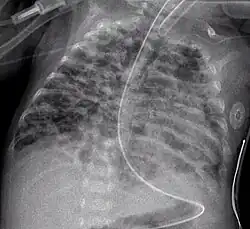

Klinische Symptome können erhöhte Atemfrequenz, vertiefte angestrengte Atmung mit Einziehungen am Brustkorb, vermehrtes Bronchialsekret, Husten, Wachstumsverzögerung und livide Haut- und Schleimhaut sein. Im Röntgenbild der Lunge finden sich u. a. diffus Überblähungsbezirke neben unzureichend belüfteten Bereichen (Atelektasen). Diagnose und Einteilung erfolgen anhand des zu einer ausreichenden Sauerstoffsättigung des Blutes notwendigen Sauerstoffbedarfs zu einem festgelegten Alter des Kindes. Definitionsgemäß ist dabei der Bedarf zum Zeitpunkt eines korrigierten Alters von 36 Schwangerschaftswochen (SSW) maßgebend. Man unterscheidet zwischen einer milden (mit 36 SSW kein erhöhter Sauerstoffbedarf mehr), moderaten (weniger als 30 % Sauerstoff in der Einatemluft notwendig) und schweren Verlaufsform (mehr als 30 % und/oder Beatmung bzw. Atemunterstützung durch CPAP notwendig).[3]